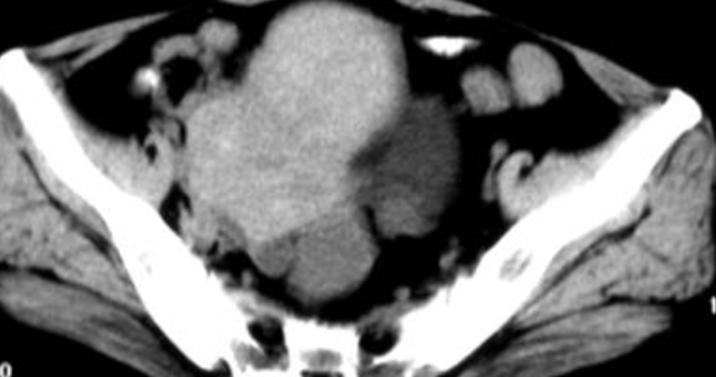

患者,47岁,2020年5月开始阴道不规则出血,起初以为是围绝经期造成的月经不调,后出血逐渐增多,淋漓不尽,患者血色素9.1,后到我院进行B超提示,子宫内膜增厚,子宫内膜实质性占位,宫腔镜提示相同,取组织4块活检,病理提示子宫内膜癌,腺癌。经过剖腹探查显示瘤子浸润子宫壁及膀胱,周围淋巴结见转移癌。于是在我院妇科行子宫及双侧附件和大网膜切除术及淋巴结清扫。术后病理提示,子宫内膜腺癌,膀胱周围淋巴结转移腺癌,分期为Ⅳ期。

患者由于大部分肿瘤组织切除的比较干净,放化疗效果还是比较肯定的,经过CT检查评定,肿瘤得到控制,没有远处转移或进展。证明我们为患者选择的这种方案,能够最大限度的控制肿瘤,同时达到副作用可控的状态。